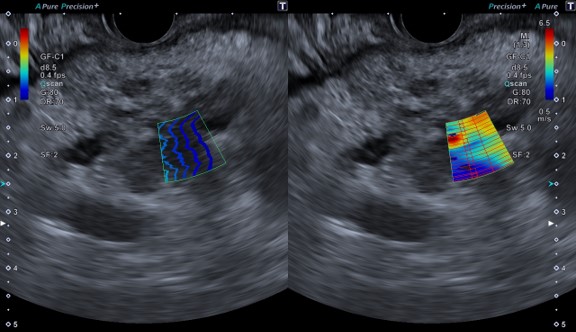

Shear wave Elastgraphy (SWE)

せん断波の伝播速度を測定し、組織の硬さを2次元的に数値やカラーマップで表示・計測を行えます。